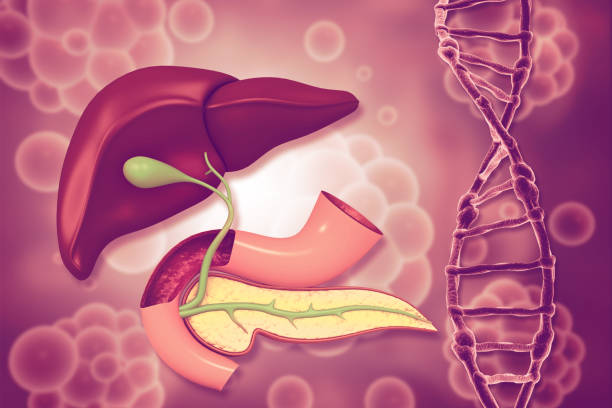

췌장과 췌장염

췌장은 복강에 위치한 중요한 내장기관 중 하나로, 소장, 대장과 같은 다른 장기와 인접해 있습니다. 췌장질염은 크게 급성췌장염과 만성췌장염으로 나뉩니다. 급성췌장염은 주로 담석이나 과음으로 인해 발생하며, 만성췌장염은 주로 음주와 흡연과 관련이 있습니다.